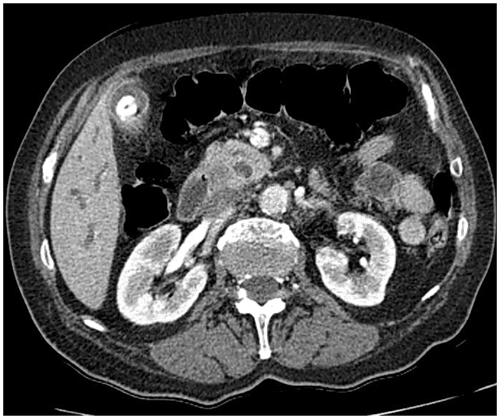

MSCT scan was performed unenhanced and on a on dynamic contrast-enhanced MDCT study with a volume of contrast medium (2mL/kg b.w) is given by rapid infusion (flow rate 4 mL/s) and MDCT is used in the parenchymal phase, with an imaging delay of aortic transit time plus 25 s, and in the venous phase (Figures 1-5). The cutoff of a distal segment of CBD and a dilatation of a CPD due to lateral compression from the pancreatic mass. The mass measured 16x10x17mm, without the infiltration of peripancreatic space. No distant metastases in the abdomen were seen, and no enlarged lymph nodes were noted.

Figure 2 Axial MDCT shows a hypoattenuating mass in the head and uncinate process of the pancreas with a dilatation of the pancreatic duct and the bile duct, and a calculus in the distal third of the gallbladder lumen.

Figure 4 Close up views of a hypoattenuating mass in the head and uncinate process of the pancreas with relatively distinct borders of the hypoattenuating mass to the surrounding pancreatic tissue.

In a patient with a painless jaundice on the US examination of the abdomen a dilated intra and extra hepatic bile ducts, dilated CPD were found as well as hypoechogenic focal lesion in the distal part of the head- processus uncinatus of the pancreas. Abdominal fusiform aneurysm was also visualized MSCT of the abdomen, unenhanced and dynamic contrast-enhanced MDCT study showed a hypoattenuating mass in the head and uncinate process of the pancreas measuring 16x10x17mm with a dilatation of the pancreatic duct and the bile duct -the double duct sign and a calculus in the distal third of the gallbladder lumen. No enlarged lymph nodes. No distant metastases